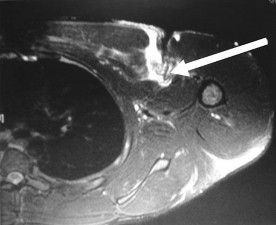

A 27-year-old professional volleyball attacker complains of subtle posterior shoulder pain and a subjective decrease in hitting power. Physical exam reveals normal active elevation, 5/5 strength in shoulder abduction, but notable weakness (3/5) in external rotation with the arm at the side. MRI of the shoulder is ordered. Based on the physical exam findings, where is the isolated neural compression most likely located, and what is the classic associated pathologic finding?

Explanation